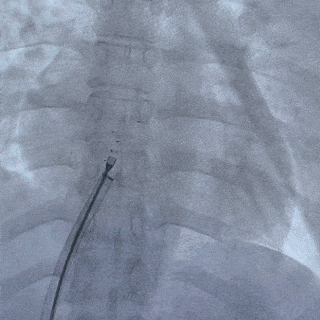

左盘面展开

前推钢缆,后撤鞘管,使左盘面3个Mark点及腰部显影点推送至鞘管外,并牵拉成型线

将封堵器和输送系统整体后撤,使左盘面贴合房间隔

释放后影像

最后封堵器盘面稳固扣合,形态扁平且位置良好,封堵成功